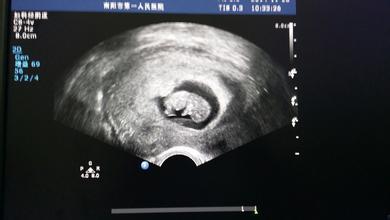

怀孕早期B超:停经6周后

在停经6周后,除了妇科常规检查之外,应通过B超确定宫内妊娠是否正常。例如宫腔内探查不到任何妊娠征象,而在子宫腔外探到异常的包块,结合其他的临床表现和实验室检查结果就可以考虑宫外孕可能。所以一般提倡于怀孕早期通过做B超明确是否是正常妊娠或双胎、葡萄胎等。

1、胎囊(GS)

胎囊也叫孕囊,胎囊只在怀孕早期见到。月经28~30天规则来潮的妇女,停经35天,B超就可以在宫腔内看到胎囊。

胎囊的位置:胎囊位置在子宫的宫底、前壁、后壁、上部、中部都属正常;形态圆形、椭圆形、清晰为正常;如胎囊为不规则形、模糊,且位置在下部,孕妇同时有腹痛或阴道流血时,可能要流产。

胎囊的大小:怀孕6周时胎囊直径约2厘米,孕10周时约5厘米,孕1.5个月时直径约2厘米,2.5个月时约5厘米为正常。